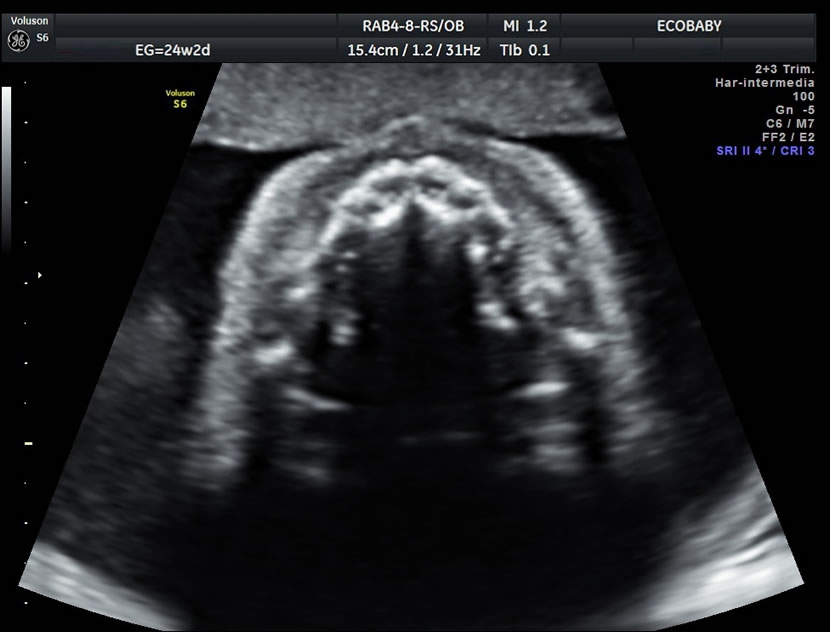

Cerebro, cuello, cara, tórax, corazón (diferentes cortes que muestran las cavidades y la correcta entrada y salida de arterias y venas), abdomen (normalidad de la pared, estómago, intestino, riñones, vejiga), miembros inferiores y superiores y columna vertebral.